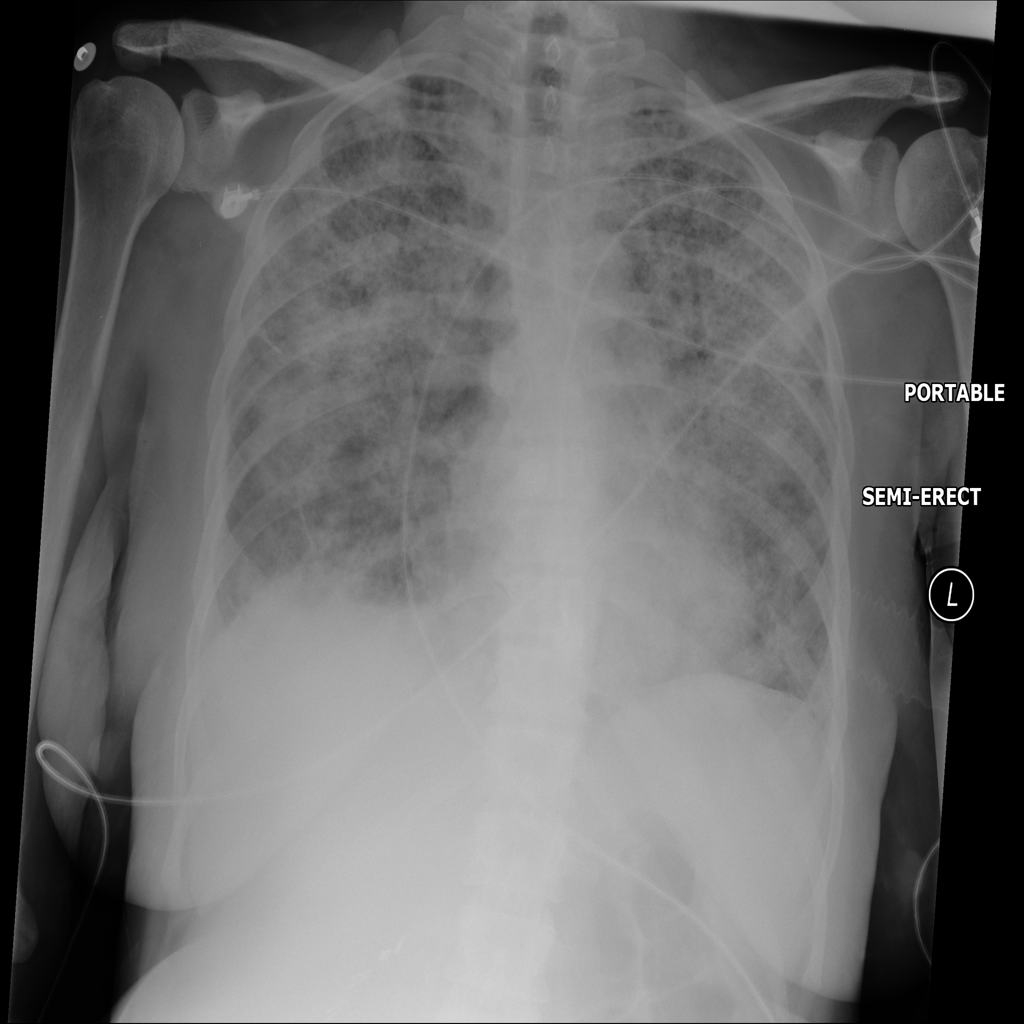

PAT-E828 · IMG-005Edema

PAT-E828 · IMG-005

AP